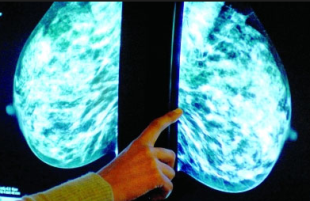

钼靶检查影像图,发现乳房深层病变?

相对于传统的乳腺钼靶检测系统,美国GE数字高清钼靶检测仪,具备,更快速、清晰,安全等信息特点,比有经验的医生更早发现早期乳腺癌病变,可提早发现0.1CM的乳房疾病微小病变。

美国GE数字高清钼靶检测仪具有照片图像清晰、对比度适宜等优点,可清楚显示乳房内小于1cm的结节性病灶,并可准确定性、定位。能检查出医师不能触及的结节,即所谓“隐匿性乳癌”和很早期的原位癌,比有经验的医师早两年发现早期乳腺癌。其辐射剂量亦降低至每人次(两侧四位)0.003Gy以下,对人体无损害。是目前诊断乳腺疾病的首选和简便、可靠的无创性检测手段。

检测效果:检测过程无痛苦,简便易行,且分辨率高,重复性好,留取的图像可供前后对比,不受年龄、体形的限制,目前已作为常规的检查。它的特点是可以检测出医生触摸不到的乳腺肿块,特别是对于大乳房和脂肪型乳房,其诊断性可达98%以上,对乳腺癌的诊断敏感性为82%~89%,特异性为87%~94%。